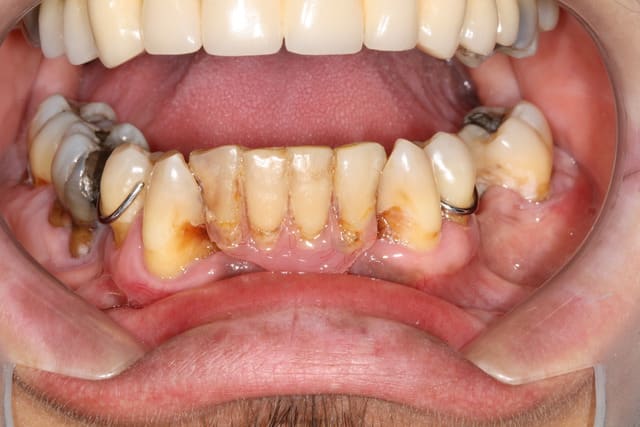

J'avais déjà vu ça mais peut-être pas tout le monde.

Étonnant que ce ne soit pas encore tout pourri en-dessous.

Je lui demanderai quand il s'est fait faire cette œuvre d'art.

Attention , j'ai volontairement déporté votre attention en haut mais en bas ...

Patient vu il y a 5 ans , et plus rien . J'ai donc traité dans l'urgence mais quoi donc ?

Indication : J'ai su préserver malgré tout le bloc incisif ...)))

Ah ... il y a des dents , 2 crochets .

Ah , c'est un appareil en bas . Quelles sont les dents de l'appareil ?

31 32 41 42 + tartre monobloc

39 45

Bonne réponse Vava .

Quelle la marque des dents ?

Le temps de la réponse est venu .

Pp ayant ouvert une banque gratuite de dents extraites , je peux m'y alimenter facilement . Certes parfois teinte et dimension sont difficiles à assortir , mais , vous pouvez encore tarifier des cavités (même composées) à la sécu en cas de récidive de carie . Coordonnées de la banque en mp .

Bon allez c'est pour rire...)))

Ce sont les dents du patient , empreinte , extractions , repositionnement dans empreinte (phase extrêmement importante , ne pas intervertir les dents;)), le prothésiste ne s'embête pas , moi non plus . Le tout est en bouche depuis 4 ans ... Il voulait du rapide en jurant qu'après ...pis le v'là aujourd'hui : "Ah ? Ca va mal ? Fallait que je reviendus ?!?!?

L'important est de satisfaire le patient , et surtout de lui "rendre service"...)))